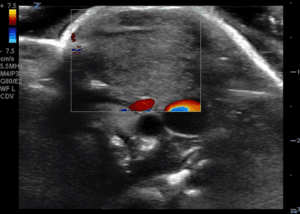

Point of Care Ultrasound (POCUS) was performed using the linear, high-frequency 12 Mhz probe by one of the authors as shown in Figures 2 and 3.

Figure 3. POCUS of neck mass.

In the left neck level VB there was a large solid mass 3.4 cm x 4.1 cm. Rounded in shape with regular borders. Vascularity was increased. There was a maintained central echogenic hilum but also other abnormal increased echogenicity centrally. There was no fluid collection or evidence of abscess formation.

Hemangiomas are congenital lesions made up of vascular tissue lined by endothelial cells. While often not present at birth they can grow rapidly within the first 3 months of life and become more prominent in size and number. Congenital cavernous haemangiomas are deeper and POCUS may reveal a cutaneous or subcutaneous soft tissue mass with prominent internal vascularity confirmed by enhanced colour flow [4].